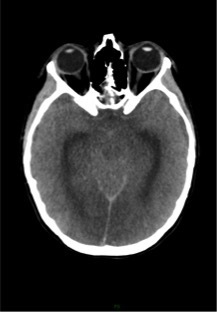

Un scanner cérébral sans injection est réalisé. Les reformations axiales vous sont présentées.

Question 10 : Ce scanner présente :

Les espaces sous sous-arachnoidiens ne sont plus visibles. Ne pas confondre la substance grise qui arrive au contact des os du crâne, avec une hyperdensité spontanée méningée.

Le volume des ventricules paraît faussement augmenté du fait de l’effacement diffus des sillons corticaux.

Qui traduit une augmentation du volume cérébral.

Aucun des deux hémisphères cérébraux ne passe sous la faux du cerveau. L’augmentation du volume cérébral est diffuse.

Effacement diffus des sillons corticaux avec début de dédifférenciation des de la substance blanche - substance grise notamment des noyaux centraux. Cela traduit un œdème cérébral diffus secondaire à un bas débit cérébral.